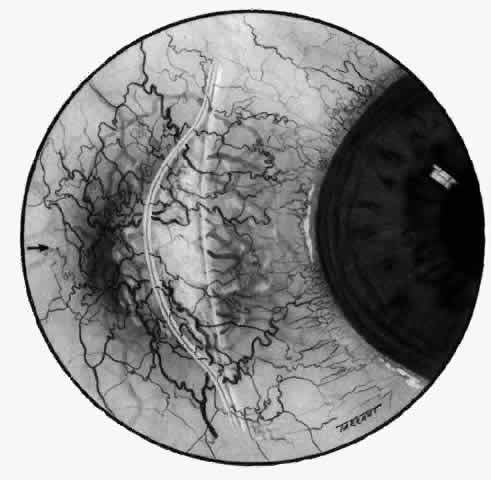

In contrast to simple episcleritis, the infiltration and edema of nodular episcleritis are localized to one part of the globe, forming a nodule and some surrounding congestion (Color Plate 1B). The nodule can be moved over the underlying sclera, which is not edematous. The scleral plexus of vessels can be distinguished deep to the nodule, lying flat on the sclera and slightly congested but otherwise normal in color and configuration (Figs. 15 and 16). Episcleral nodules may be single or multiple but do not undergo necrosis (see Fig. 16). After multiple attacks of nodular episcleritis in the same location, the superficial lamellae of the sclera show some alteration and become slightly more transparent in this one area.

Although patients with nodular anterior scleritis resemble those with nodular episcleritis on cursory examination, detailed examination reveals marked differences. The nodule or nodules (they may be multiple) consist of scleral tissue that is immovable episclera is tightly adherent to the nodule, which is tender to the touch. Although the sclera sometimes becomes transparent below the nodule, it does not become necrotic, nor does the condition extend beyond the site of the nodule, as occurs in necrotizing scleral disease (Fig. 36).

(see Fig. 28; Figs. 34 and 35). The edematous